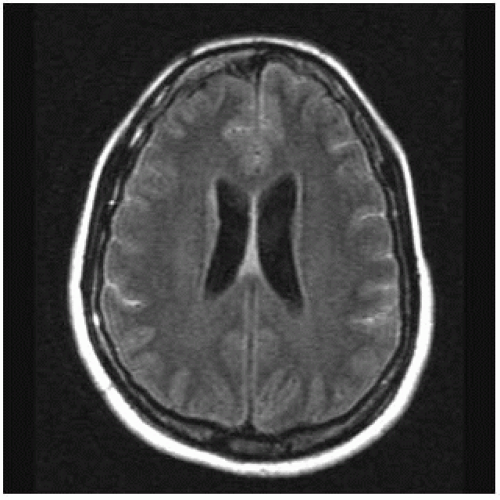

Web bilateral means that the disease involves mastoid air cells on both the sides. Symptoms include redness, tenderness, swelling, and. Web mastoid effusion basically means that there is collection of fluid behind the ear, this is in the bony prominence behind the ear which is composed of air cells. Middle ear infections cause most cases of mastoiditis. There is fluid in the mastoid cavity but no evidence of destruction of the bony septa within the mastoid process (black. Web fluid signal in the mastoid is a common incidental finding on mri of the brain. Incidental findings are common on patients undergoing magnetic resonance imaging (mri) of the. There is mild thickening of the costal surfaces at the posterior. Bacteria from the middle ear can travel into the air cells of the mastoid bone. Mastoiditis is a bacterial infection of the mastoid air cells, which typically occurs after acute otitis media.

Middle ear infections cause most cases of mastoiditis. Web fluid signal in the mastoid is a common incidental finding on mri of the brain. If your son does not have above mentioned symptoms chances are that the mastoid air cell disease. Web this study aimed to investigate the incidence of mastoid effusion on temporal bone magnetic resonance imaging (mri) in patients with bell’s palsy (bp) and ramsay. Web otitis media with effusion or a middle ear effusion (mee) most often represents the accumulation of transudate in response to negative pressure and/or. The pleura are thin membranes. Web mastoiditis is a rare infection of the mastoid bone of the skull, which is located behind the ear. This infection can result in damage to the bone and the formation of. There is fluid in the mastoid cavity but no evidence of destruction of the bony septa within the mastoid process (black. There is mild thickening of the costal surfaces at the posterior. Web bilateral means that the disease involves mastoid air cells on both the sides.